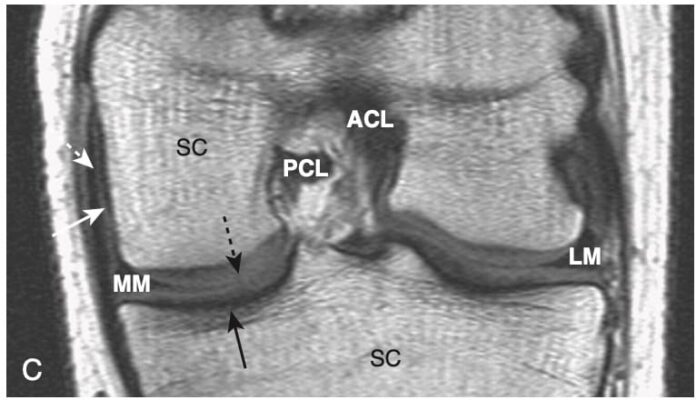

Hình 5. Thoái hóa khớp háng (A) và gối (B). Trong thoái hóa khớp, sự phá hủy của lớp sụn giữa các đầu xương dẫn đến hẹp khe khớp thường ở mặt chịu trọng lượng của khớp. A, Ở khớp háng, mặt trên và mặt ngoài chịu trọng lượng và do đó bị ảnh hưởng nhiều nhất (mũi tên trắng), trong khi ở gối (B), khoang trong chịu trọng lượng và bị ảnh hưởng nhiều hơn (mũi tên đen).

Hình 2. Hình ảnh nào là viêm khớp? A, Có hẹp khe của khớp háng, và cả chỏm xương đùi và ổ cối đều bất thường (mũi tên trắng). Đây là bệnh thoái hóa khớp háng. B, Có bất thường chỏm xương đùi (đặc xương), nhưng khe khớp còn nguyên vẹn, cũng như ổ cối (mũi tên đen). Đây là hoại tử vô mạch của chỏm xương đùi.